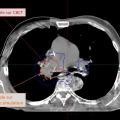

Le dépistage, le diagnostic et la prise en charge des cancers les plus fréquents, tels que le cancer du sein, de la prostate, du poumon et colo–rectal, reposent sur des avancées majeures en imagerie médicale. Grâce à des techniques performantes comme la mammographie, l’imagerie par résonance magnétique (IRM) multiparamétrique, la…

Dans le cadre de la prise en charge des cancers, la radiothérapie joue un rôle central, constituant une modalité de traitement utilisée chez plus de la moitié des patients à un moment de leur parcours thérapeutique. Bien qu’elle soit une composante essentielle des soins oncologiques, ses aspects techniques et ses évolutions récentes…